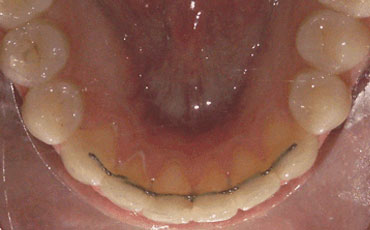

Anni successivi: controlli ogni 6 mesi degli apparecchi di contenzione fissi o mobili (sono quelle procedure che si mettono in atto per mantenere i risultati ottenuti con la terapia ortodontica ed evitare recidive).

Bimbi e denti: meno rischio di carie con la "sigillatura dei solchi"14 aprile 2016Una fase importantissima in ogni trattamento di ortodonzia è quella della così detta "contenzione"; si tratta di quelle metodiche che vengono attuate per far si che i denti allineati e raddrizzati con tanta fatica rimangano dritti nel tempo.